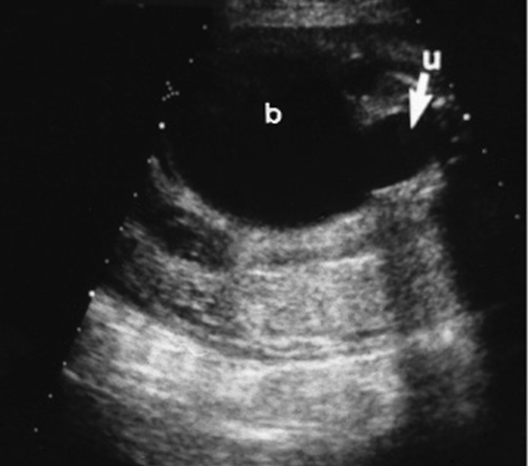

Urachal cyst

Urachal Dilation